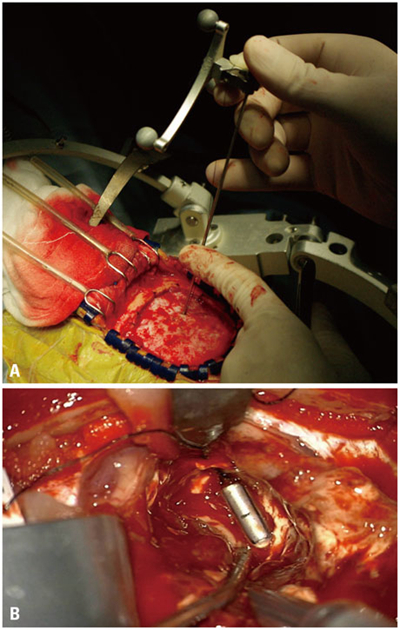

顱內血腫圖片

硬膜下血腫 (7)

硬膜下血腫 (8)

硬膜下血腫 (9)